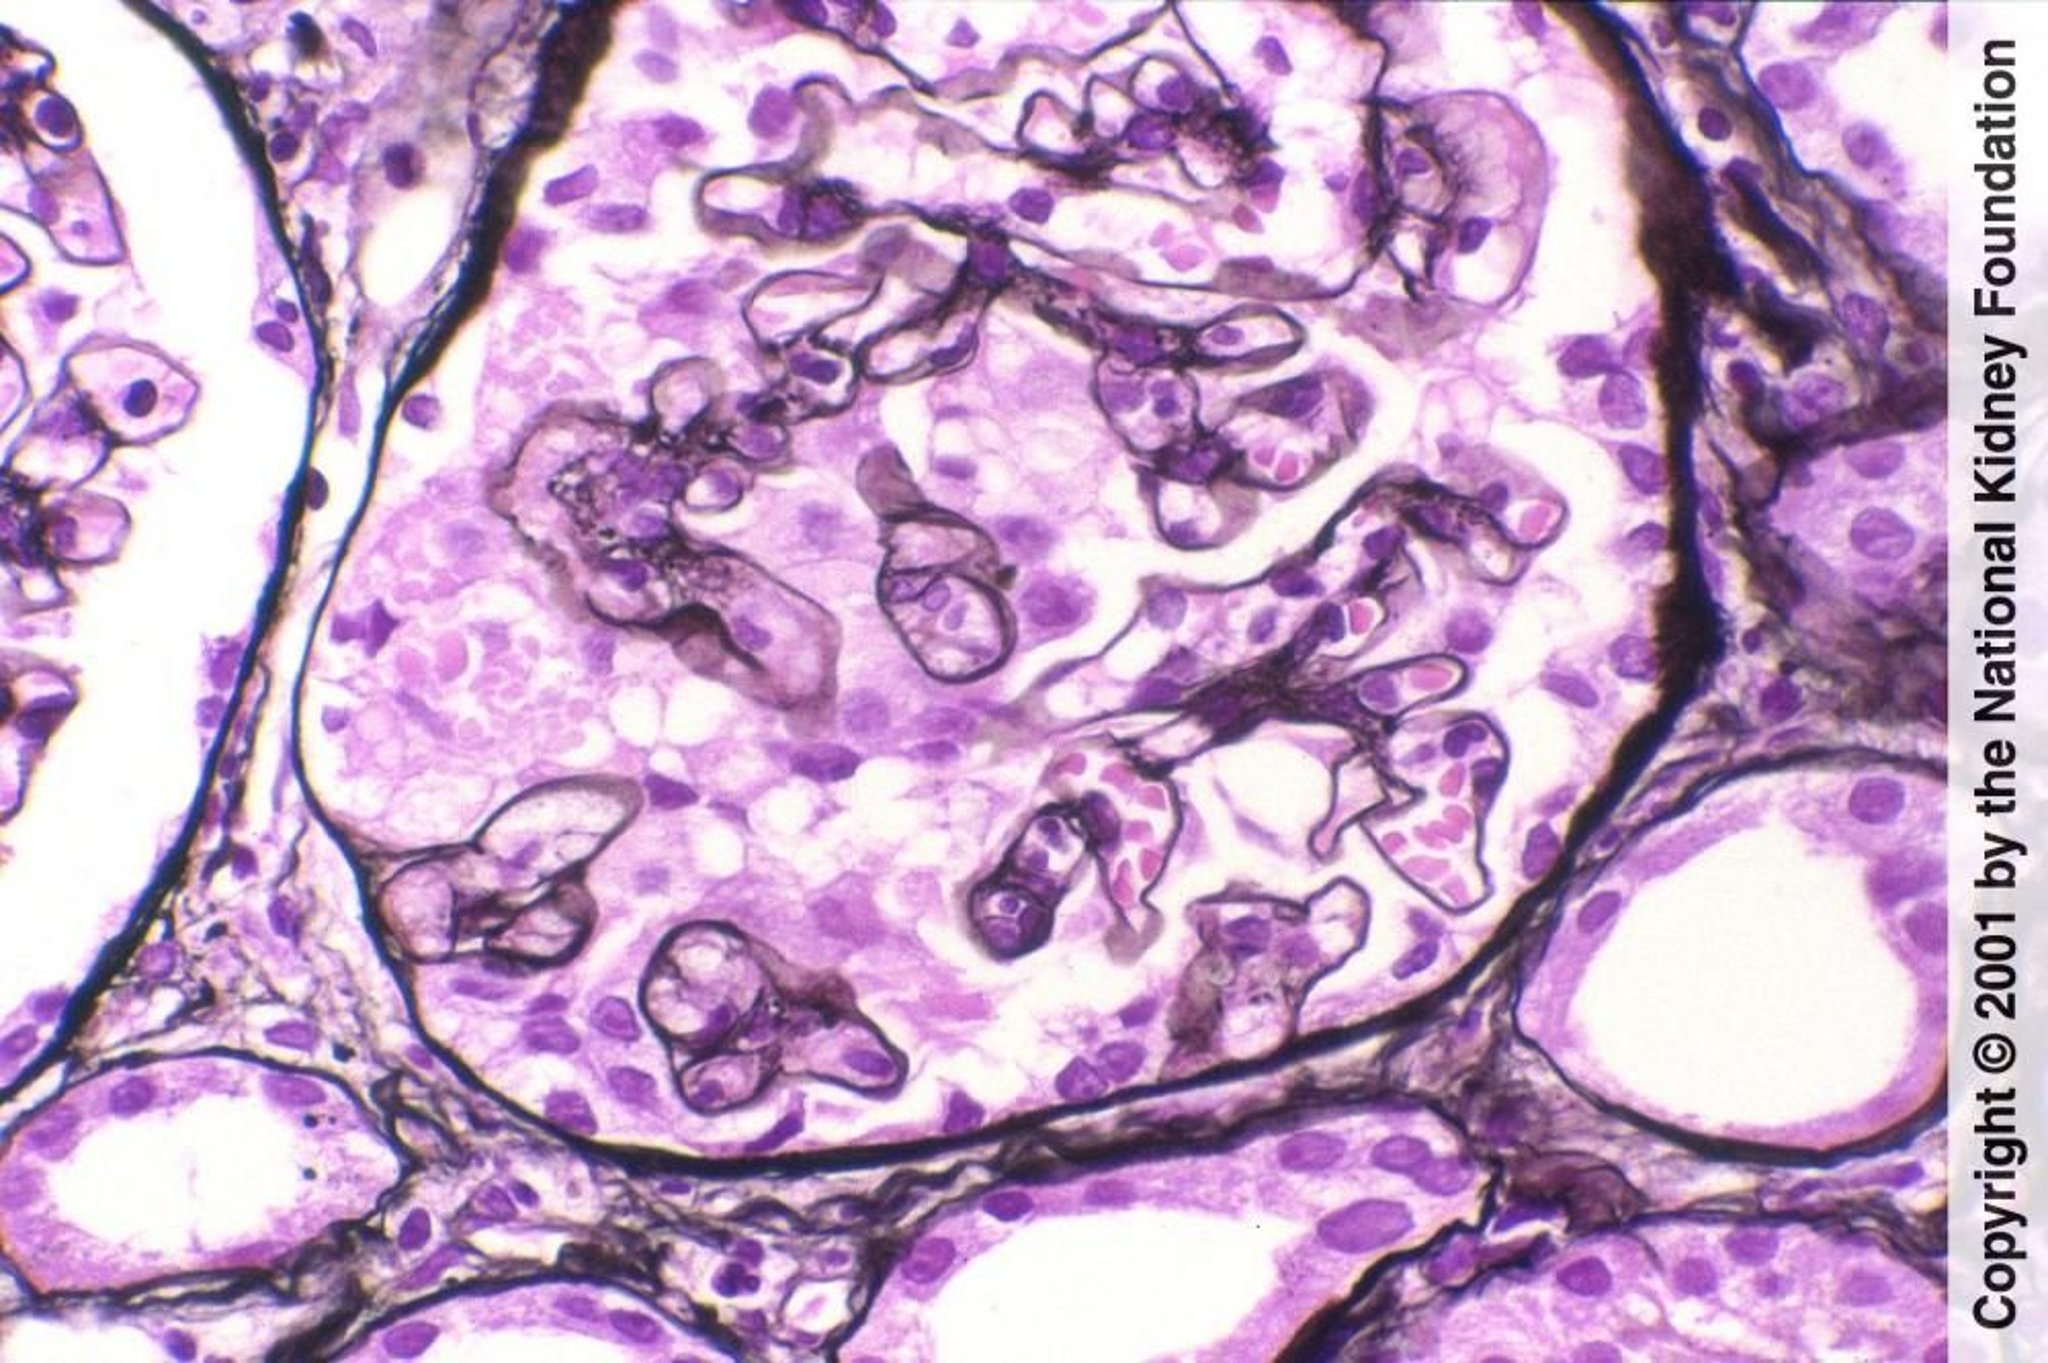

Gesichert wird die Diagnose durch eine Nierenbiopsie, die eine fokale und segmentale Hyalinisierung der Glomeruli zeigt, bei Immunfärbung oft mit einer IgM- und Komplement (C3)-Ablagerung in einem knotigen und grob granulären Muster. Die Elektronenmikroskopie kann eine diffuse Auslöschung von Podozyten bei idiopathischen Fällen zeigen, aber lückenhafte Auslöschungen bei sekundären Fälle. Es kann eine allgemeine Sklerose sichtbar sein, zusammen mit sekundären atrophischen Glomeruli. Die Biopsie kann falsch-negativ sein, wenn Bereiche von fokalen Veränderungen nicht abgetastet werden.

Das obere Bild zeigt die rechte Seite des Glomerulus. Der Glomerulus, der segmental sklerotisch ist, besteht aus verödeten Kapillarlumina und einer erhöhten Menge an Mesangialmatrix. Der Rest des Glomerulus ist normal (Jones-Silberfärbung, ×400). Im unteren Bild ist Hyalin, definiert als glattes, glasig aussehendes Material (das Gegenteil von Exsudation), das aus der Insudation von Plasmaproteinen resultiert. Sie tritt häufig auf und ist nicht diagnostisch (Jones-Silberfärbung, ×400).

Das obere Bild zeigt die rechte Seite des Glomerulus. Der Glomerulus, der segmental sklerotisch ist, besteht aus veröde

Image provided by Agnes Fogo, MD, and the American Journal of Kidney Diseases' Atlas of Renal Pathology (see www.ajkd.org).